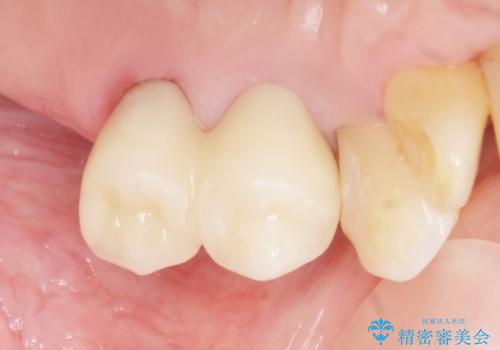

気にされていた歯の動揺や違和感がなくなり、喜んで頂けました。

モチベーションがあがり、大臼歯欠損部位の治療に関しても前向きに検討して下さるとの事でした。

クラウンの種類:オールセラミッククラウン スタンダード

- ¥506,000 (再根管治療×2本、土台×2本、仮歯×2本、クラウン×2本) ※税込費用は治療当時の料金となります